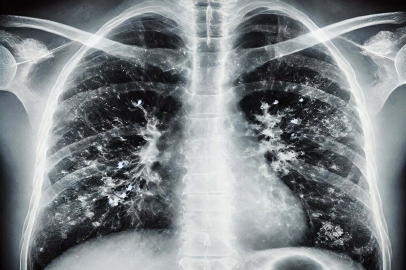

İzmir İl Sağlık Müdürlüğü Halk Sağlığı Hizmetleri Başkanlığı Başkan Yardımcısı Doktor Metin Kızılelma, kış aylarında havaların soğumasıyla birlikte solunum yolu enfeksiyonlarında artış yaşanmasının doğal bir süreç olduğunu belirterek, vatandaşlara alınması gereken önlemler konusunda önemli uyarılarda bulundu.

Soğuk havaların etkisiyle kapalı alanlarda daha fazla vakit geçirildiğini hatırlatan Dr. Kızılelma, bu durumun virüslerin yayılımını kolaylaştırdığını ifade etti. Özellikle hasta bireylerin kapalı ve kalabalık ortamlarda maske kullanmasının, enfeksiyonların yayılmasını önemli ölçüde azaltabileceğini belirten Kızılelma, hasta olmayan kişilerin de kalabalık alanlarda maske takmasının koruyucu bir önlem olabileceğini söyledi.

Solunum yolu enfeksiyonlarının farklı etkenlere bağlı olarak değişken şiddette seyredebildiğini ifade eden Kızılelma, hastalık sürecinde bol sıvı tüketimi ve dinlenmenin hayati önem taşıdığını söyledi. Ateş yüksekliği, şiddetli öksürük ve genel durum bozukluğu yaşayan kişilerin mutlaka bir sağlık kuruluşuna başvurması gerektiğini vurguladı.